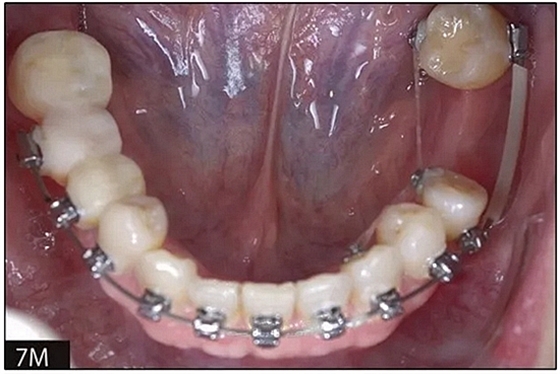

完全固定的Damon Q設(shè)備(加利福尼亞州Glendora的Ormco)與制造商指定的弓絲和附件一起使用。下頜弓,一開(kāi)始放入0.014英寸的鎳鈦弓絲,5個(gè)月后放入0.014×0.025英寸的鎳鈦弓絲。舌側(cè)扣和鏈圈放置在下頜尖牙和第二前磨牙上以控制扭轉(zhuǎn)。在治療的第7個(gè)月,將下頜弓絲換成0.017× 0.025英寸的β鈦絲。另一個(gè)舌側(cè)扣和鏈圈放置在下頜左側(cè)第三磨牙上以提供近中牽引力(圖9)。在16個(gè)月的治療結(jié)束時(shí),所有的扭轉(zhuǎn)都得到了矯正,缺牙間隙縮小到8 mm(圖8),但由于頰側(cè)骨板的嚴(yán)重吸收,牙槽嵴的寬度仍然很窄(約3 mm)(圖9)。通過(guò)正畸移動(dòng)下頜左側(cè)第二前磨牙,在前磨牙之間產(chǎn)生一個(gè)種植部位。在第一和第二前磨牙之間的弓絲上放置一個(gè)推簧,并將舌側(cè)扣和鏈圈放置在第一前磨牙和第三磨牙之間(圖9),在頰側(cè)和舌側(cè)施加力。施力均為輕力,每個(gè)表面上約2盎司(28.3 cN)以控制牙根側(cè)面的吸收。

圖8

圖9

圖10.經(jīng)過(guò)7個(gè)月后,以每月1毫米的速度牽引下頜左側(cè)第二前磨牙,正畸產(chǎn)生的種植部位長(zhǎng)約7毫米。通過(guò)使用固定矯治器保持間隙6個(gè)月。根尖X線片顯示第二前磨僅有少量牙根遠(yuǎn)中面吸收。